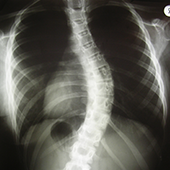

A betegség a gerinc bármelyik szakaszán előfordulhat és ennek megfelelően különböző elváltozások jönnek létre. Leggyakrabban a háti szakaszon jelentkezik a betegség, itt a fokozott háti domborulat, ún. kerekhát deformitás jön létre. Ha a betegség az ágyéki szakaszon fordul elő, akkor az élettani görbületek elsimulnak, és ún. laposhát vagy botgerinc alakul ki. A betegség területén a gerincszakasz mozgása korlátozott, spontán fájdalom, fáradékonyság, nyomásérzékenység jelentkezhet. A röntgenen található jellegzetes elváltozások: a csigolyatest elülső része laposabbá válik (ún. ékcsigolya), a zárólemez és a porckorong elváltozásai következtében kis csomócskák (Schmorl-csomók) láthatóak a röntgenképen.

Röntgenvizsgálat:

Ha a gerinc szagittális görbületeinek fent leírt változásait észleljük, feltétlenül szükséges a kétirányú gerincfelvétel. A röntgenfelvétel alapján lehet eldönteni, hogy hanyag tartásról vagy Scheuermann-kórról van-e szó. Álló helyzetben az egész gerincről készült felvétel jól mutatja a görbületek nagyságát és elhelyezkedését. Fekvő helyzetben a gerinc mobilitását, rugalmasságát tudjuk vizsgálni.